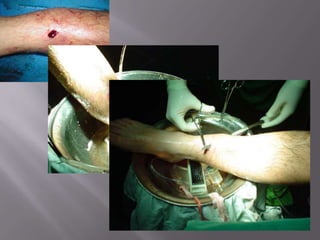

Fractura de PiernaIndicaciones del tto. quirúrgico:Fractura expuesta.

Obesidad(relativa)Fractura de PiernaMétodo de fijación:Tutor externo.

Placa y tornillos.

Clavo endomedular: (goldstandar)